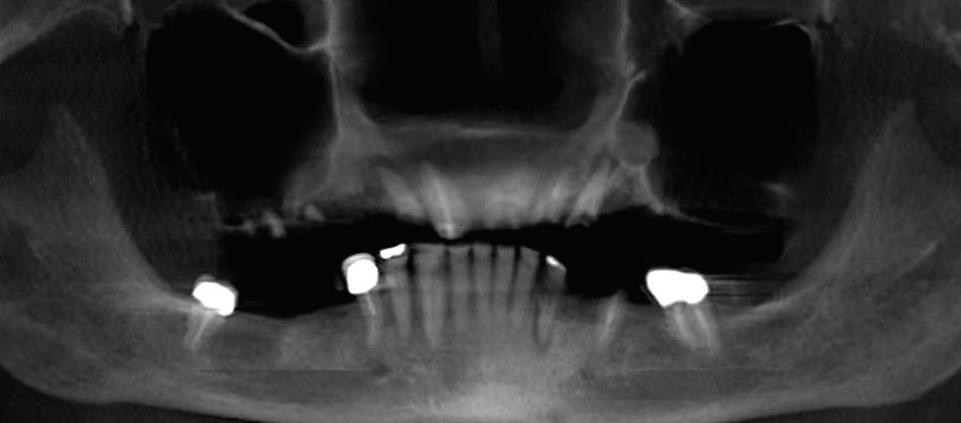

Can just four implants replace all of the teeth on the top or the bottom of your mouth? Thanks to advances in dental implant technology, that answer is a resounding yes.

Tooth loss is extremely common among adults, especially as we age. Rather than living with the discomfort and hassles of dentures, many people are opting for what is called “all-onfour” dental implant restoration.

An implant is a small titanium

screw that fits inside your jawbone and replaces the root-part of a missing tooth. Minor surgery is required to insert the implants. Once the implant is in place, a crown is attached to give you a highly realistic-looking and functional prosthetic tooth.

You do not need a dental implant for each and every one of your missing teeth. All you need is four precisely placed implants on the top of your mouth, and four on the bottom, to restore your full smile. That’s the beauty of the all-on-four. And because the implant is made of titanium, it has the unique ability to fuse to living bone and function as part of it. So eventually, the dental implant becomes part of the jawbone and serves as a strong, longlasting foundation for your new teeth.

Besides ensuring that your implants are permanently fixed in place, this bone fusion has another important benefit: it prevents future bone loss in the jaw. This helps to maintain a more youthful facial structure – and better